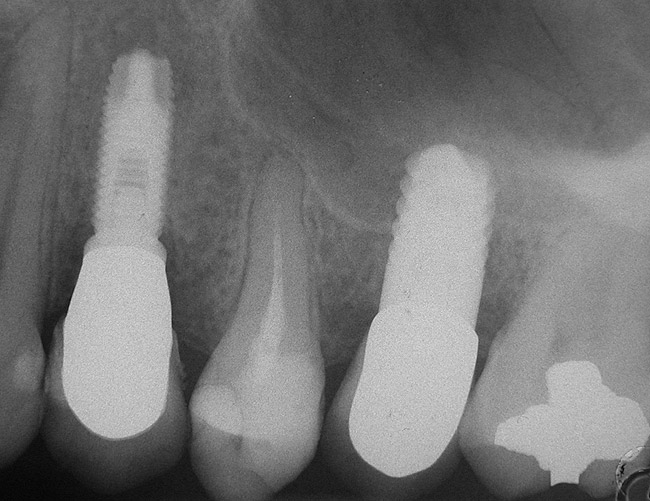

Second-stage surgery was performed after 4 months (Figure 8); healing abutments were placed and the soft tissue was allowed to heal for 5 more weeks. Then, splinted porcelain-fused-metal (PFM) crowns supported by custom gold abutments were delivered (Figure 9 and Figure 10).

Figure 8  At 4 months after treatment, the radiograph revealed the presence of a bone layer surrounding the implant.

Figure 10  Posttreatment radiograph, after cementation of the final restorations.